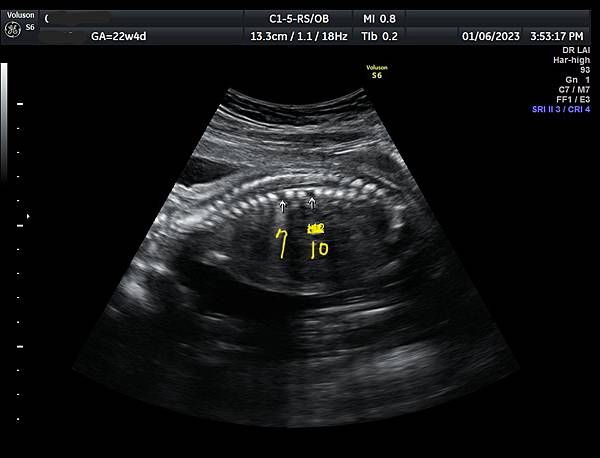

孕兒診所賴錫鉅醫師 394《用生命影響生命》: 產前診斷蝴蝶椎案例分享

產前診斷蝴蝶椎案例分享

產前診斷蝴蝶椎 (1)